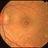

- macular hole, full thickness macular hole

Fundus camera

Topcon VT-50 - Description

- Elderly white female with a Stage IV, full-thickness macular hole OS with whitish deposits visible at the base of the hole and a surrounding cuff of subretinal fluid